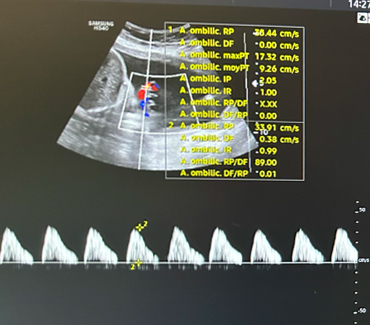

À 30 SA, Mme L. consulte aux urgences adressée par son échographiste avec la courbe de croissance et les images suivantes.

Figure 1 (Rodolphe Matias de Sousa, La Revue du Praticien)

Il existe une franche cassure de la courbe, le fœtus est passé au troisième percentile. L’échographie en figure 1 est un écho-Doppler de l’artère ombilicale. Elle montre une diastole ombilicale nulle. Il s’agit donc d’un RCIU et non d’un fœtus petit pour l’âge gestationnel.

Concernant l’échographie de vitalité fœtale (figure 3), elle décrit :

– l’analyse du Doppler de l’artère ombilicale qui témoigne des échanges entre le fœtus et la mère (par ordre de gravité : diastole ombilicale positive normale ; diastole ombilicale nulle ; reverse-flow) ;

– l’analyse du Doppler de l’artère cérébrale moyenne qui peut mettre en évidence une redistribution cérébro-placentaire ou une anémie fœtale.